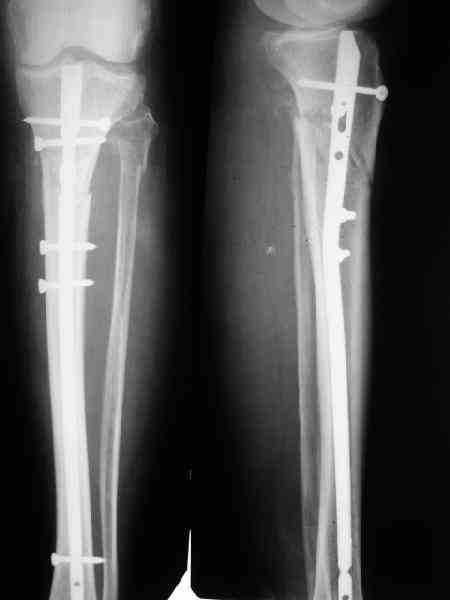

Спицы оставлять не надо. Надо их убрать, но перед этим ввести винт-poller. Такая необходимость возникает в редких случаях, когда можно ожидать смещения длинного отломка. Спицы из короткого отломка после введения запирающих винтов можно удалять без риска смещения.

В приложении пример, дистальный отломок пружинил кзади. Два винта потому, что первый оказался чуть кпереди и не упирался в гвоздь.